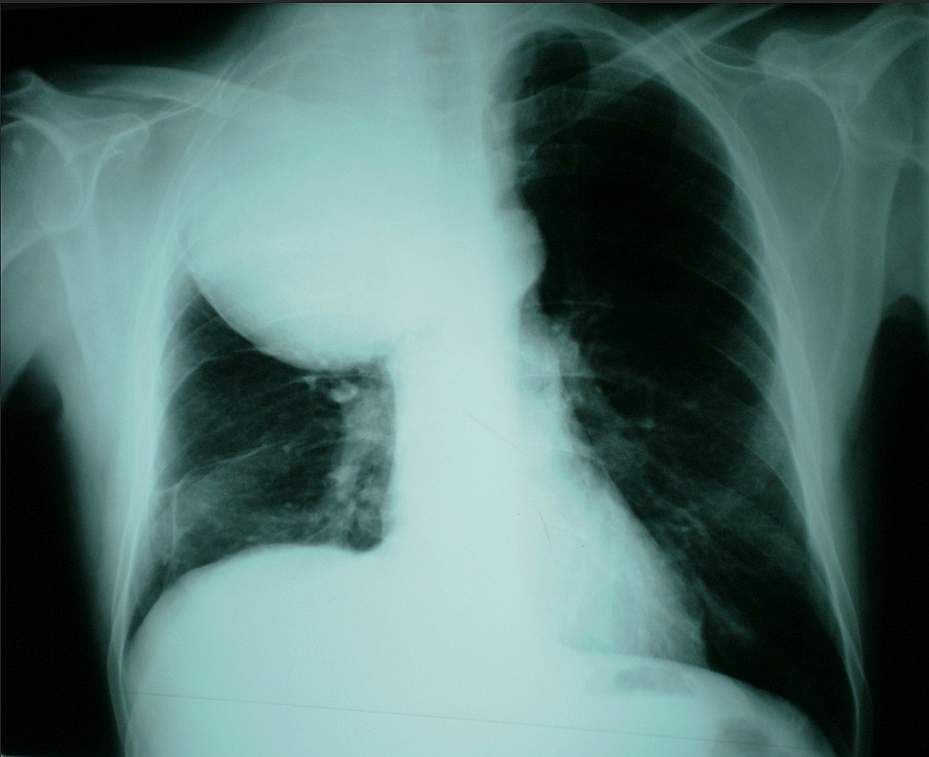

On the chest radiograph, a large sharply marginated mass with uniform opacity was demonstrated projected over the right upper lung. CT and MR imaging was recommended for confirming the localization of the mass to either the lung or the pleura and for more details of the tumour appearance.